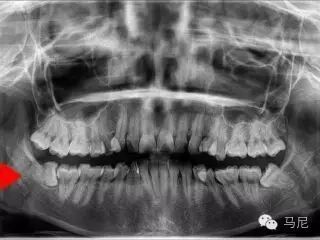

拔牙前的风险和难度预判非常重要。术者需要在拔牙前应针对病人主诉问题进行详细口内检查、仔细确认所需拔除的牙齿,了解患牙情况及其与邻牙、周围组织的关系。所有患者常规均应行术前X线片检查,对于根尖片无法满足手术需要的病例,则需进一步拍摄牙科CT,了解牙齿形态、结构及与周围重要解剖结构(如上颌窦、下颌神经管等)的位置关系。术前与患者及家属进行良好的交流和沟通,交代拔牙术过程及术中、术后的相关事项,以缓解患者的紧张、恐惧心理,取得其信任与配合。对于高度紧张或牙科恐惧症患者,术前应采用镇痛、镇静等措施,以达到心理、精神的微创。此外,根据术前预判和设计,准备合适的微创拔牙器械。

难易度最高的深埋横卧智齿